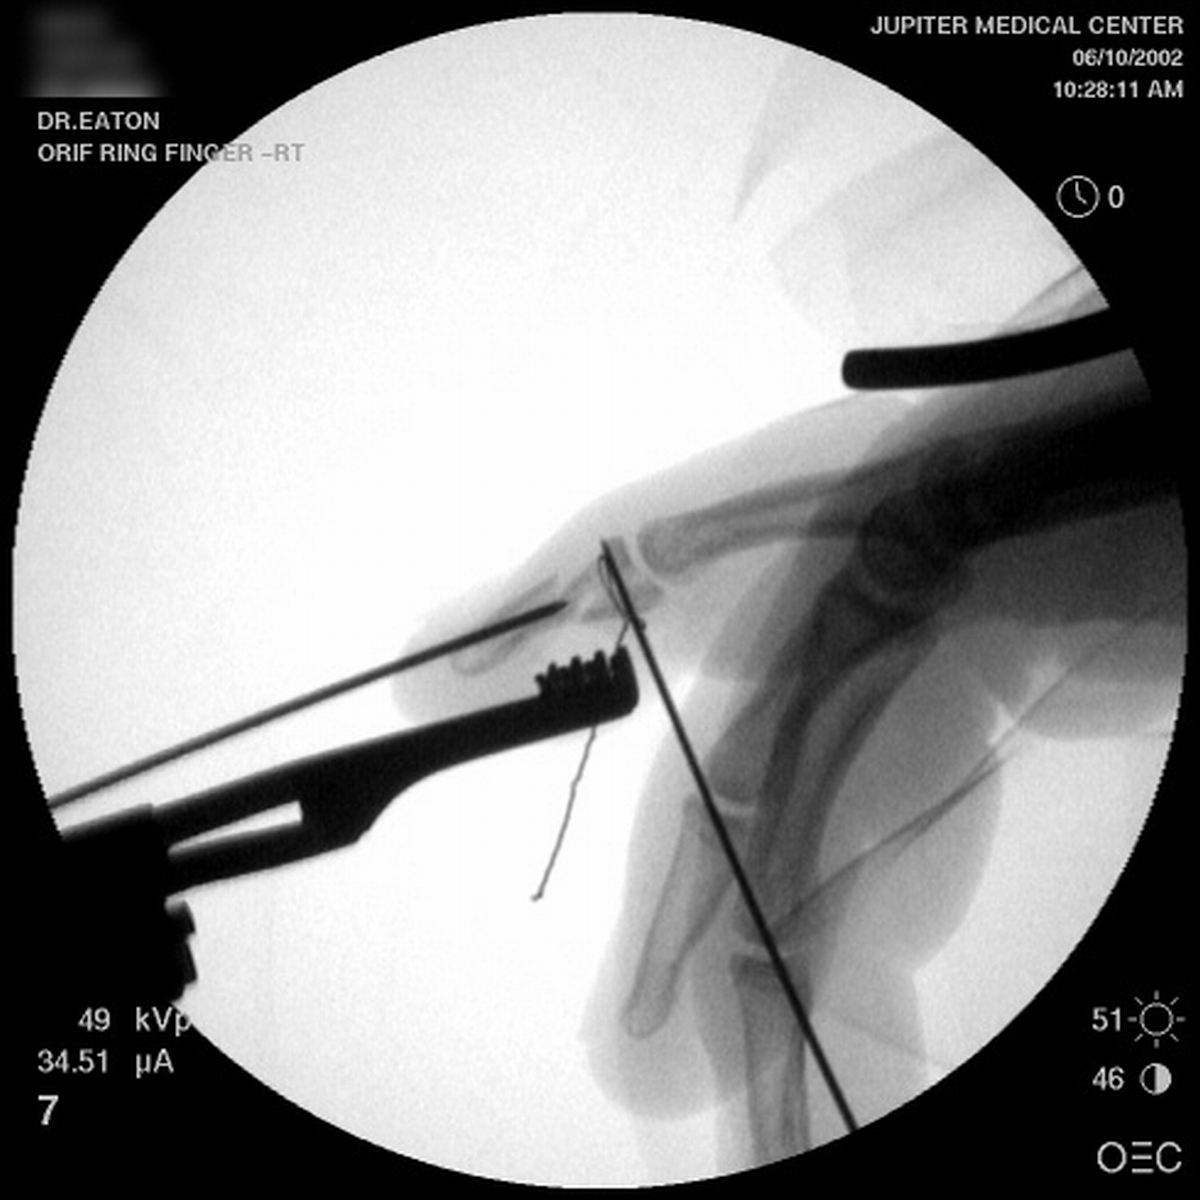

| A midline longitudinal palmar approach was used. This view shows a transverse pin across the dorsal proximal fragment, to be used as a path for interosseous wiring. Additional pins have been placed across each single cortex for later advancement. |